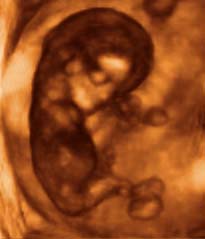

Mostanra babád teste, belső és külső szervei szinte teljesen kifejlődtek. A szív most már literszámra pumpálja a vért a baba testében. Az érzőidegek és a gerincvelő is fejlődésnek indul, mostantól a baba fájdalmat is érez. Bár az agya még közel sem akkora, mint majd születésekor, a felépítése már ugyanolyan. Az ujjak elkülönültek, a haj és a köröm pedig egyre csak növekszik. Magzatod most már 6.5-9 cm hosszú, súlya pedig 12-14 gramm.

A külső nemiszervek egyre jobban felismerhetők. Bár eddig szinte csak reflexmozgásokra volt képes, mostantól a kicsi akaratlagosan mozog! Ám ezt még mindig nem lehet érezni, főleg nem az első várandósság során. Az orvosnál már saját fülünkkel is hallhatjuk gyermekünk szívverését (zsebkendőt érdemes vinni). Olyan gyorsan ver, mintha egy vonat zakatolna vagy egy ló vágtázna odabent. Ha már volt szerencséd meghallgatni ezt a hangot, megnyugodhatsz, ezzel a vetélés kockázata jelentősen csökkent.

Mit mutat az ultrahang?